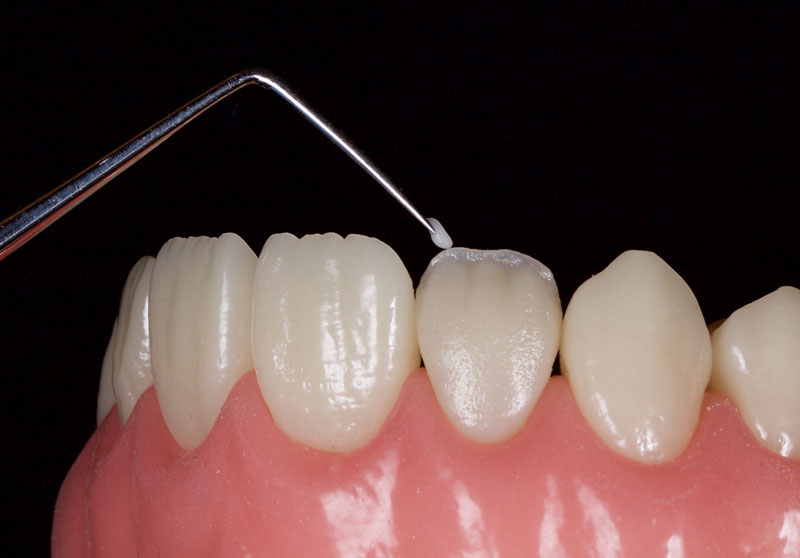

If appropriate, a highly translucent opalescent enamel mass can be modeled sparingly at the incisal edge, for example OBN, Micerium (Fig. 13).